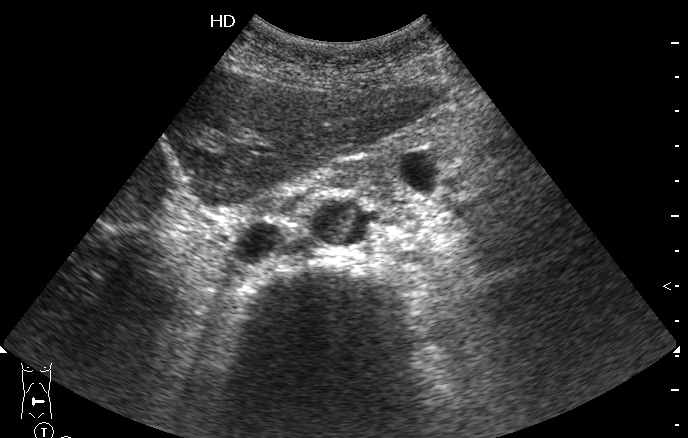

УЗИ: тромбоз инфраренального отдела аорты

Пожилая женщина, поступила в БСМП с резкими болями в ногах. Пульс на бедренных артериях отсутствует.

Поперечный скан аорты

Назначено консервативное лечение, назавтра появился кровоток в бедренных артериях.